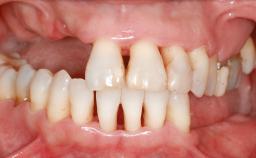

A 45-year-old woman with a completely edentulous maxilla was referred to evaluate the possibility of rehabilitation with an implant-supported prosthesis. This patient was healthy and a non-smoker. She had been wearing a maxillary complete denture opposing a natural mandibular dentition since her twenties. This situation had resulted in progressive resorption of the alveolar ridge, repeatedly creating a need for relining the denture. Twenty years later, despite multiple adaptations and the use of “glues” the denture was unstable and causing the patient psychological and functional discomfort.

Defining Characteristics Fully edentulous upper jaw to be rehabilitated with an implant-borne fixed dental prosthesis

Loading Protocol Conventional or early

Retention Screw-retained, with 4 or more splinted implants Screw-retained, with 4 or more splinted implants